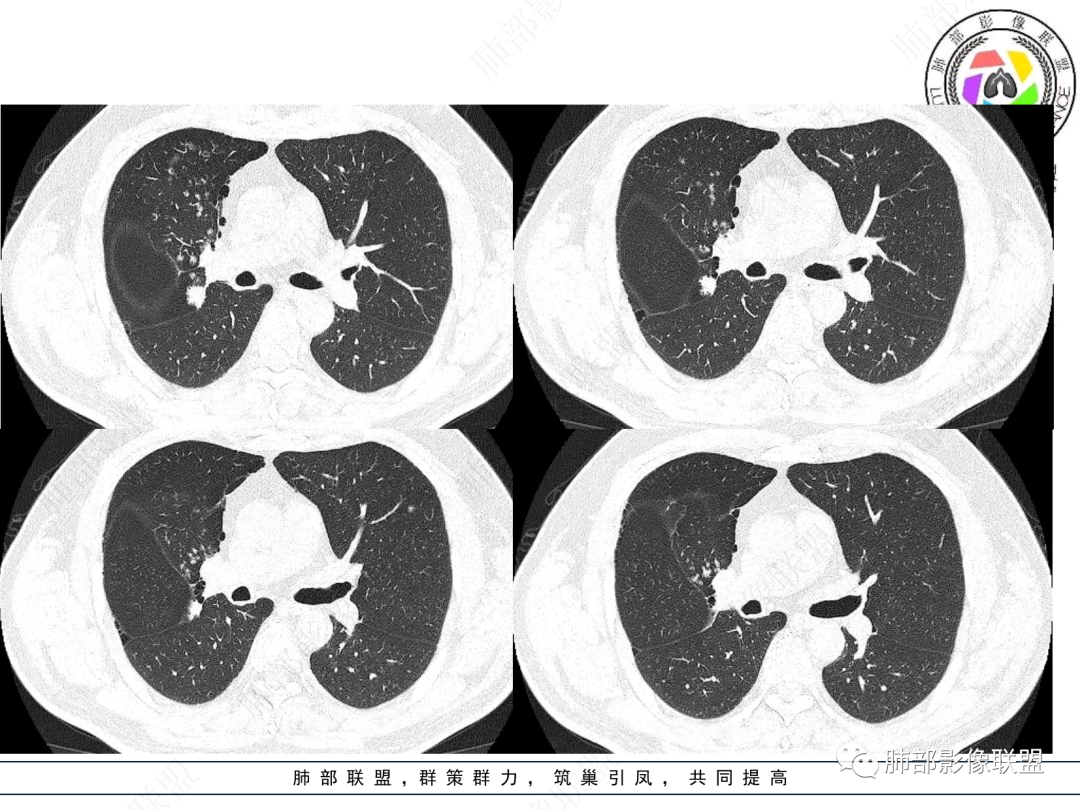

男,52。间断咳嗽、咳痰2周,加重3天。胸部CT:右主、右上叶支气管多发软组织影,跳跃不连续,内可见小环状高密度,点状钙化,管壁破坏,上叶支气管堵塞,远端分支粘液栓,可见小支气管管壁增厚、管腔狭窄,沿支气管分布多发结节,无大片炎症不张。考虑:TB?NTM?鉴别Ca并阻塞性炎症。

中年男性,咳嗽咳痰,右肺上叶近肺门肿块,上叶支气管近端阻塞,内有粘液栓,右肺上叶多发结节影有小空泡,沿支气管血管束分布,血象不高,CRP及PCT不高,XPERT阴性,结核可能性不大,考虑恶性肿瘤可能,类癌?腺样囊性癌?鳞癌?远端肺内的考虑阻塞性炎症还是转移?

右肺上叶支气管开口见阻塞物影及强化,息肉样向腔内外浸润性生长,并有颗粒钙化,右肺上叶段支气管主干增粗及密度增高,见指套征,支气管血管旁见多发小斑点,小斑片影阻塞性炎性病灶〈小花小草表现〉,支气管镜示新生物血供丰富(结核完全排除),方向恶性,符合鳞癌特点,与小细胞Ca鉴定,临床专科支气管镜取材活检明确诊断。

腔内肿物,强化不均匀,强化程度为轻中度强化(CT值增加25HU),且强化特点为快进快出,右肺上叶支气管责任区域的阻塞性炎症加痰栓(气管镜也证实右上叶支气管内痰多)。这些均明确指向鳞癌。

一点不异常啊,分布在阻塞责任气管区域的支气管增粗伴腺泡结节(细支气管腔内及肺泡内阻塞性炎症伴痰栓),只不过还没有大片实变而已。@韩平     临沂市人民医院呼吸科

远端支气管腔内不强化的是粘液栓,强化的是肿瘤。

影像上分析的观察点:腔内、壁、腔外、远端,然后就是远端肺组织、淋巴结、肺血管、胸膜、其他肺部,这个人就是阻塞性炎症为主。